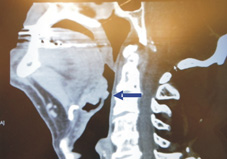

所有的病人在六週內都可以恢復正常飲食,如果術後需要進行放射線治療,則可以降低劑量,大大減少治療後吞嚥困難的比例。另外針對下咽與喉部腫瘤的切除,利用機器手臂手術也大大提供器官保留的機會,以及降低氣管切開手術的比例,使的患者術後還能保有說話的功能。至於咽喉癌復發的治療,機器手臂手術也提供了一項新的治療途徑,因為復發後若進行二度的放射線治療,往往療效不佳且會造成骨頭或軟組織壞死等等更大的後遺症。除了腫瘤的疾病以外,這項技術也可應用在打呼和阻塞性呼吸中止症的患者身上,用經口機器手臂手術可輕易完成過去手術器械無法完成的舌根扁桃體(如:圖三)微創切除,已有文獻報告顯示單單進行舌根扁桃體微創切除可以有效讓呼吸中止的次數平均減少六成,並且成效遠優於現行的舌根部射頻燒灼手術。

圖三、左圖為磁振造影顯示舌根扁桃體造成的呼吸道狹窄(箭頭處),右圖則為手術中所見之肥厚舌根扁桃體(箭頭處)